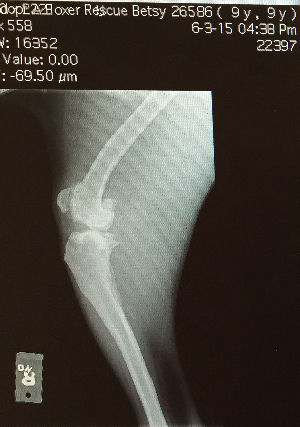

Betsy has a pronounced limp

and her former owner told AABR that she had torn her ACL at some point in

the past. Betsy went to the Veterinary Referral and Emergency Center a

few days ago to have her knees evaluated. We found out that Betsy has

severe arthritis in both knees. It is much worse in the left, but

still very bad in the right also - which is the result of damage to her

ligaments that had never been addressed. Unfortunately, the arthritis

in now irreversible and Betsy is not a candidate for surgery. For the

rest of her many years, she will have to rely on pain management and joint

supplements to maintain a quality of life. Betsy also has corneal

ulcers in both eyes which have healed over, causing vision impairment.

It is sad news for Betsy, but at least her pain can now be addressed and she

will never suffer neglect again.